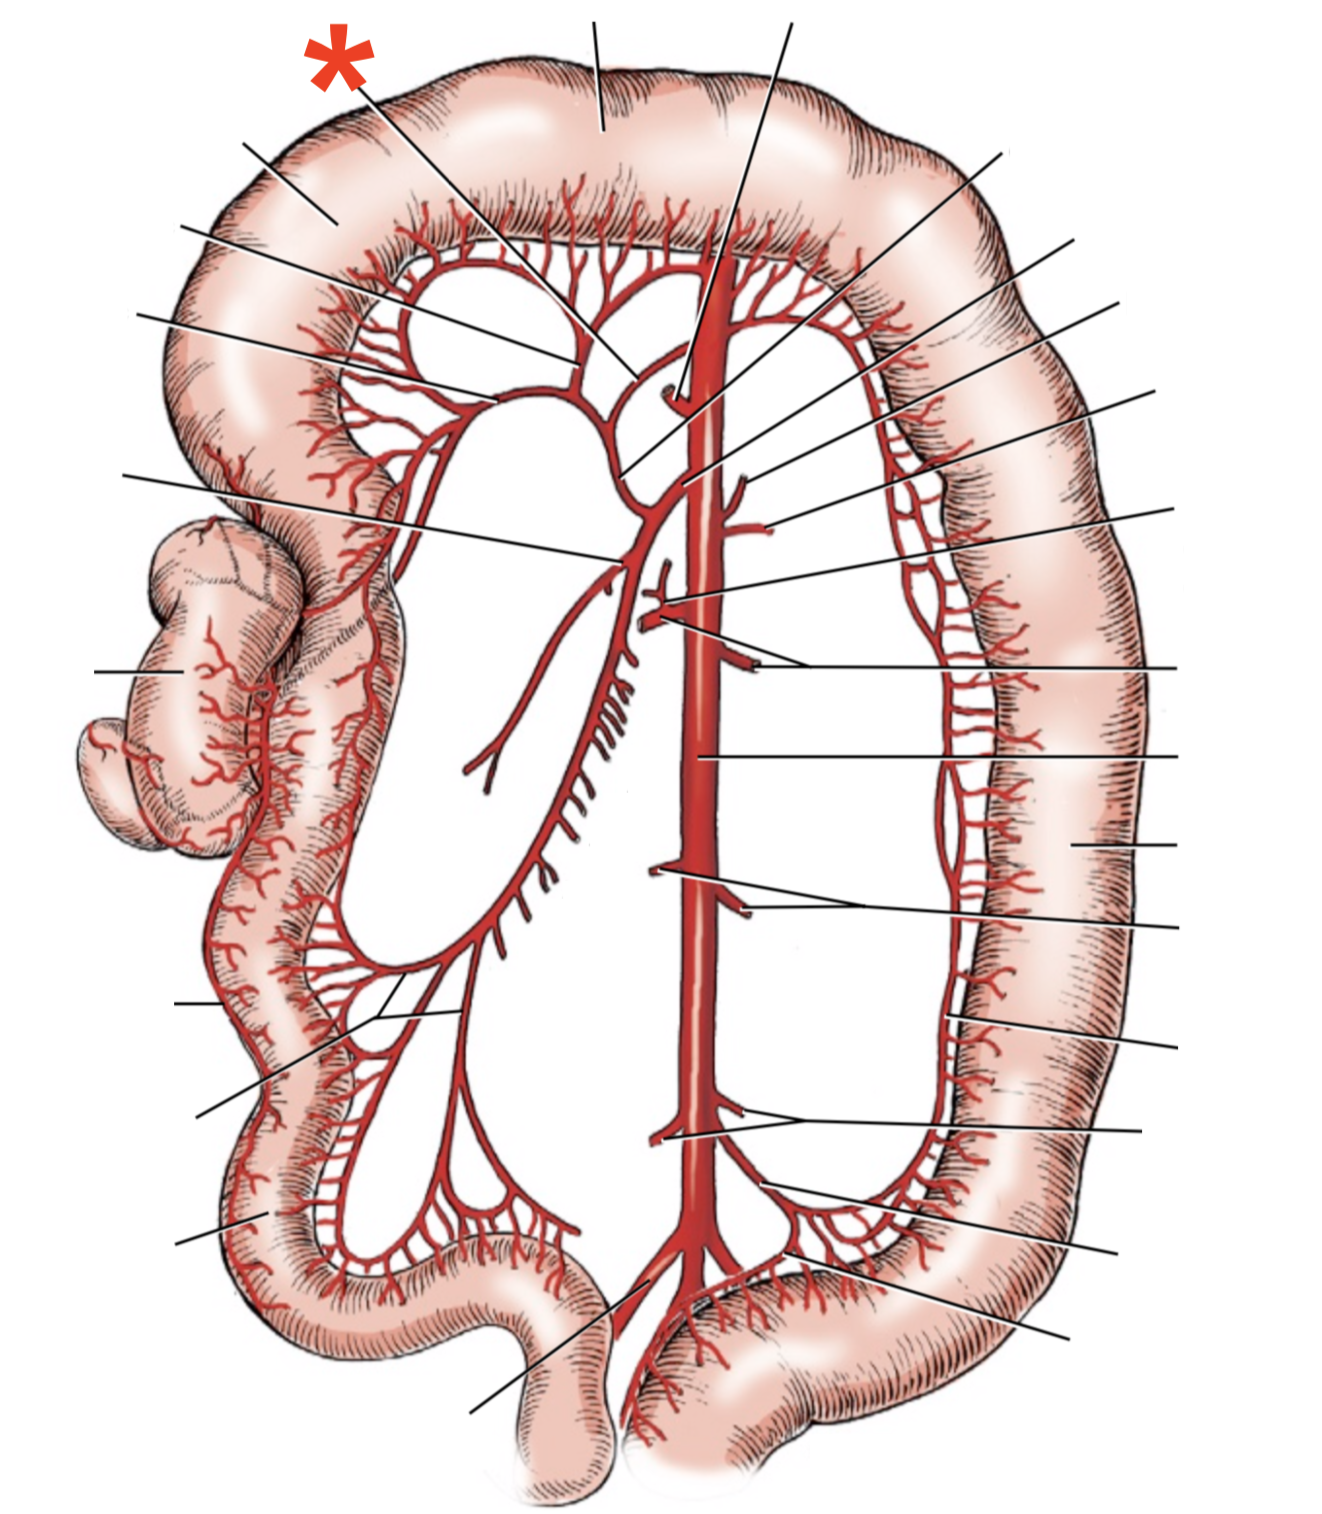

13

Q

A

A. mesenterica cranialis

15

Q

A

A. pancreaticoduodenalis caudalis

16

Q

A

Aa. jejunales

17

Q

A

A. ilei

- Anastomises with r. ileus mesenterialis a. iliocolica

18

Q

A

A. ileocolica

19

Q

A

A. colica dextra

20

Q

A

A. colica media

21

Q

A

A. mesenterica caudalis

22

Q

A

A. colica sinistra

23

Q

A

A. rectalis cranialis

List the branching of *a.* *mesenterica* *caudalis*

* *A. colica sinistra*

* *A. rectalis cranialis*

List the branches of *a.* *mesenterica* *cranialis*

* *A.* *pancreaticoduodenalis* *caudalis*

* *Aa. jejunalis*

* *A. ilei*

* Common trunk

* A. colica media

* A. colica dextra

* *A. ileocolica*

* *R. ilei mesenterialis*

* *A. cecalis*

* *R. colicus*